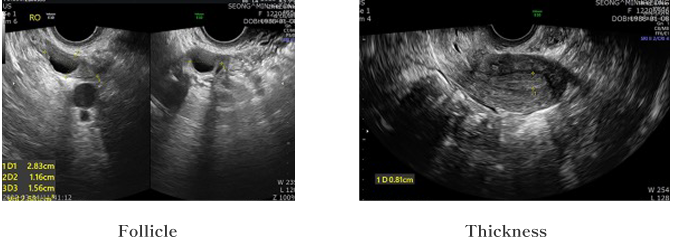

一方で、先進国を含む多くの国々では、幹細胞や上清液エクソソームを併用した不妊治療の臨床が進められており、静脈注射や卵巣への直接投与によって、卵巣の機能を促進し、妊娠率を高める研究が行われています。

実際に、当IVF医療チームが早期閉経不全症(POI)患者に対して臨床治療を行った結果、33%の妊娠効果が確認されました。

韓国CHA病院での臨床治療結果によると

6名中2名の患者において、臍帯由来幹細胞を1回静脈投与した後、18〜24週間で臨床的な改善効果が認められました。

- 卵巣における役割は以下のとおりです。卵胞周囲の微小血管形成を促進し、 卵胞の成長 および排卵過程を支援します。その結果、低酸素状態にある卵巣環境を改善し、組織再生を誘導するとともに、血流増加によって栄養および酸素供給を改善し、卵胞の維持に寄与します。

- 卵巣における役割は、卵胞内の細胞増殖および分化(特に顆粒膜細胞を促進することです。損傷した卵巣組織の回復を誘導し、血管新生およびECM(細胞外マト リックス)の再構築にも寄与します。また、微小環境の回復にも貢献します。

- 卵巣に関連する役割は以下の通りです。FSHに対する顆粒膜細胞の反応性を高め、排卵を誘導します。子宮内膜の厚みを増加させ、着床に適した環境を整えます。